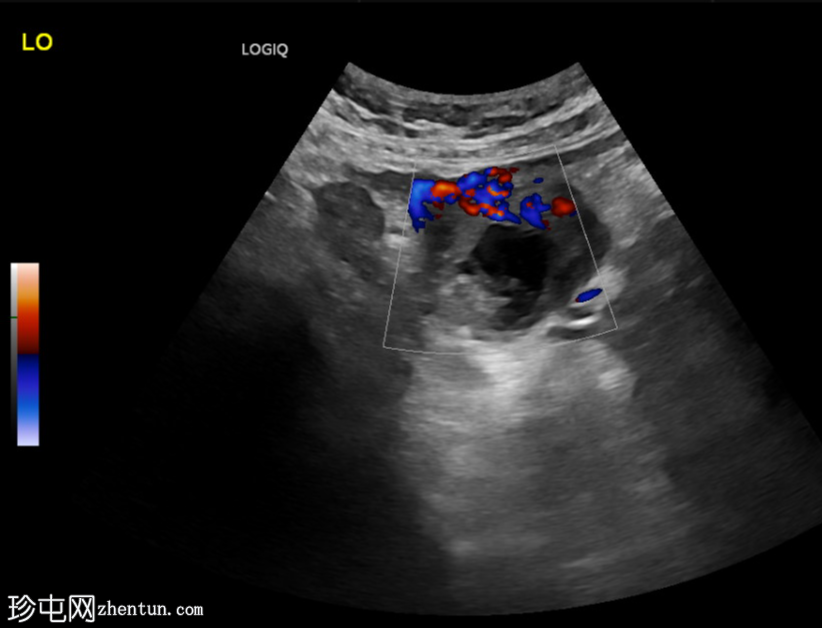

斜切面

左侧卵巢明显增大,可见一囊肿,大小约3.2 x 2.3 cm,呈火环征,可能为黄体囊肿。左侧卵巢与子宫之间可见一管状结构,直径约1.3 cm,内含浑浊液体,未见血管,最可能为输卵管积血。以上特征提示可能为左侧异位妊娠。

未见宫内妊娠囊。